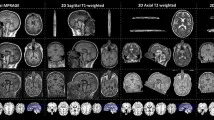

Рисунок 1